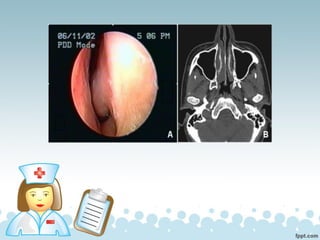

PÓLIPOS NASALES

Los pólipos nasales son unas formaciones

blanquecinas que aparecen en el interior de las fosas

Estos pólipos son benignos, pero pueden crecer hasta el punto

de llegar a obstruir completamente las fosas nasales.

Los síntomas más habituales son:

✓ Alteración del olfato (anosmia)

✓ Aumento de mucosidad nasal

✓ Dificultad para respirar

✓ Ronquidos